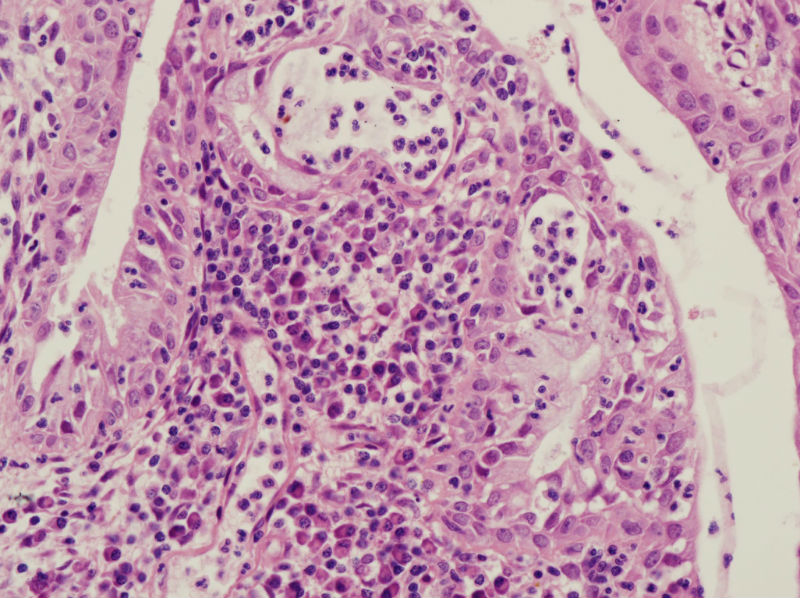

45岁,宫颈息肉?请老师指教

慢性炎,腺体有鳞化

宫颈及宫颈内膜息肉,腺体增生及鳞化,鳞化跟中药没有关系,跟炎症刺激有关系。

宫颈息肉伴腺体鳞化,微腺体增生

宫颈息肉伴腺体的鳞化,我个人感觉息肉的分型比较复杂,有的地方存在宫颈腺体增生型,有些地方血管型,还有纤维型也可见。

宫颈息肉伴糜烂,局部腺体及黏膜上皮鳞状上皮化生。至于说具体分型,与临床治疗和预后都没有关系,可以不分。

Benign endocervical polyp with SM and MGH. You do not need classify benign endocervical polyp because it has no impact on clinical management.